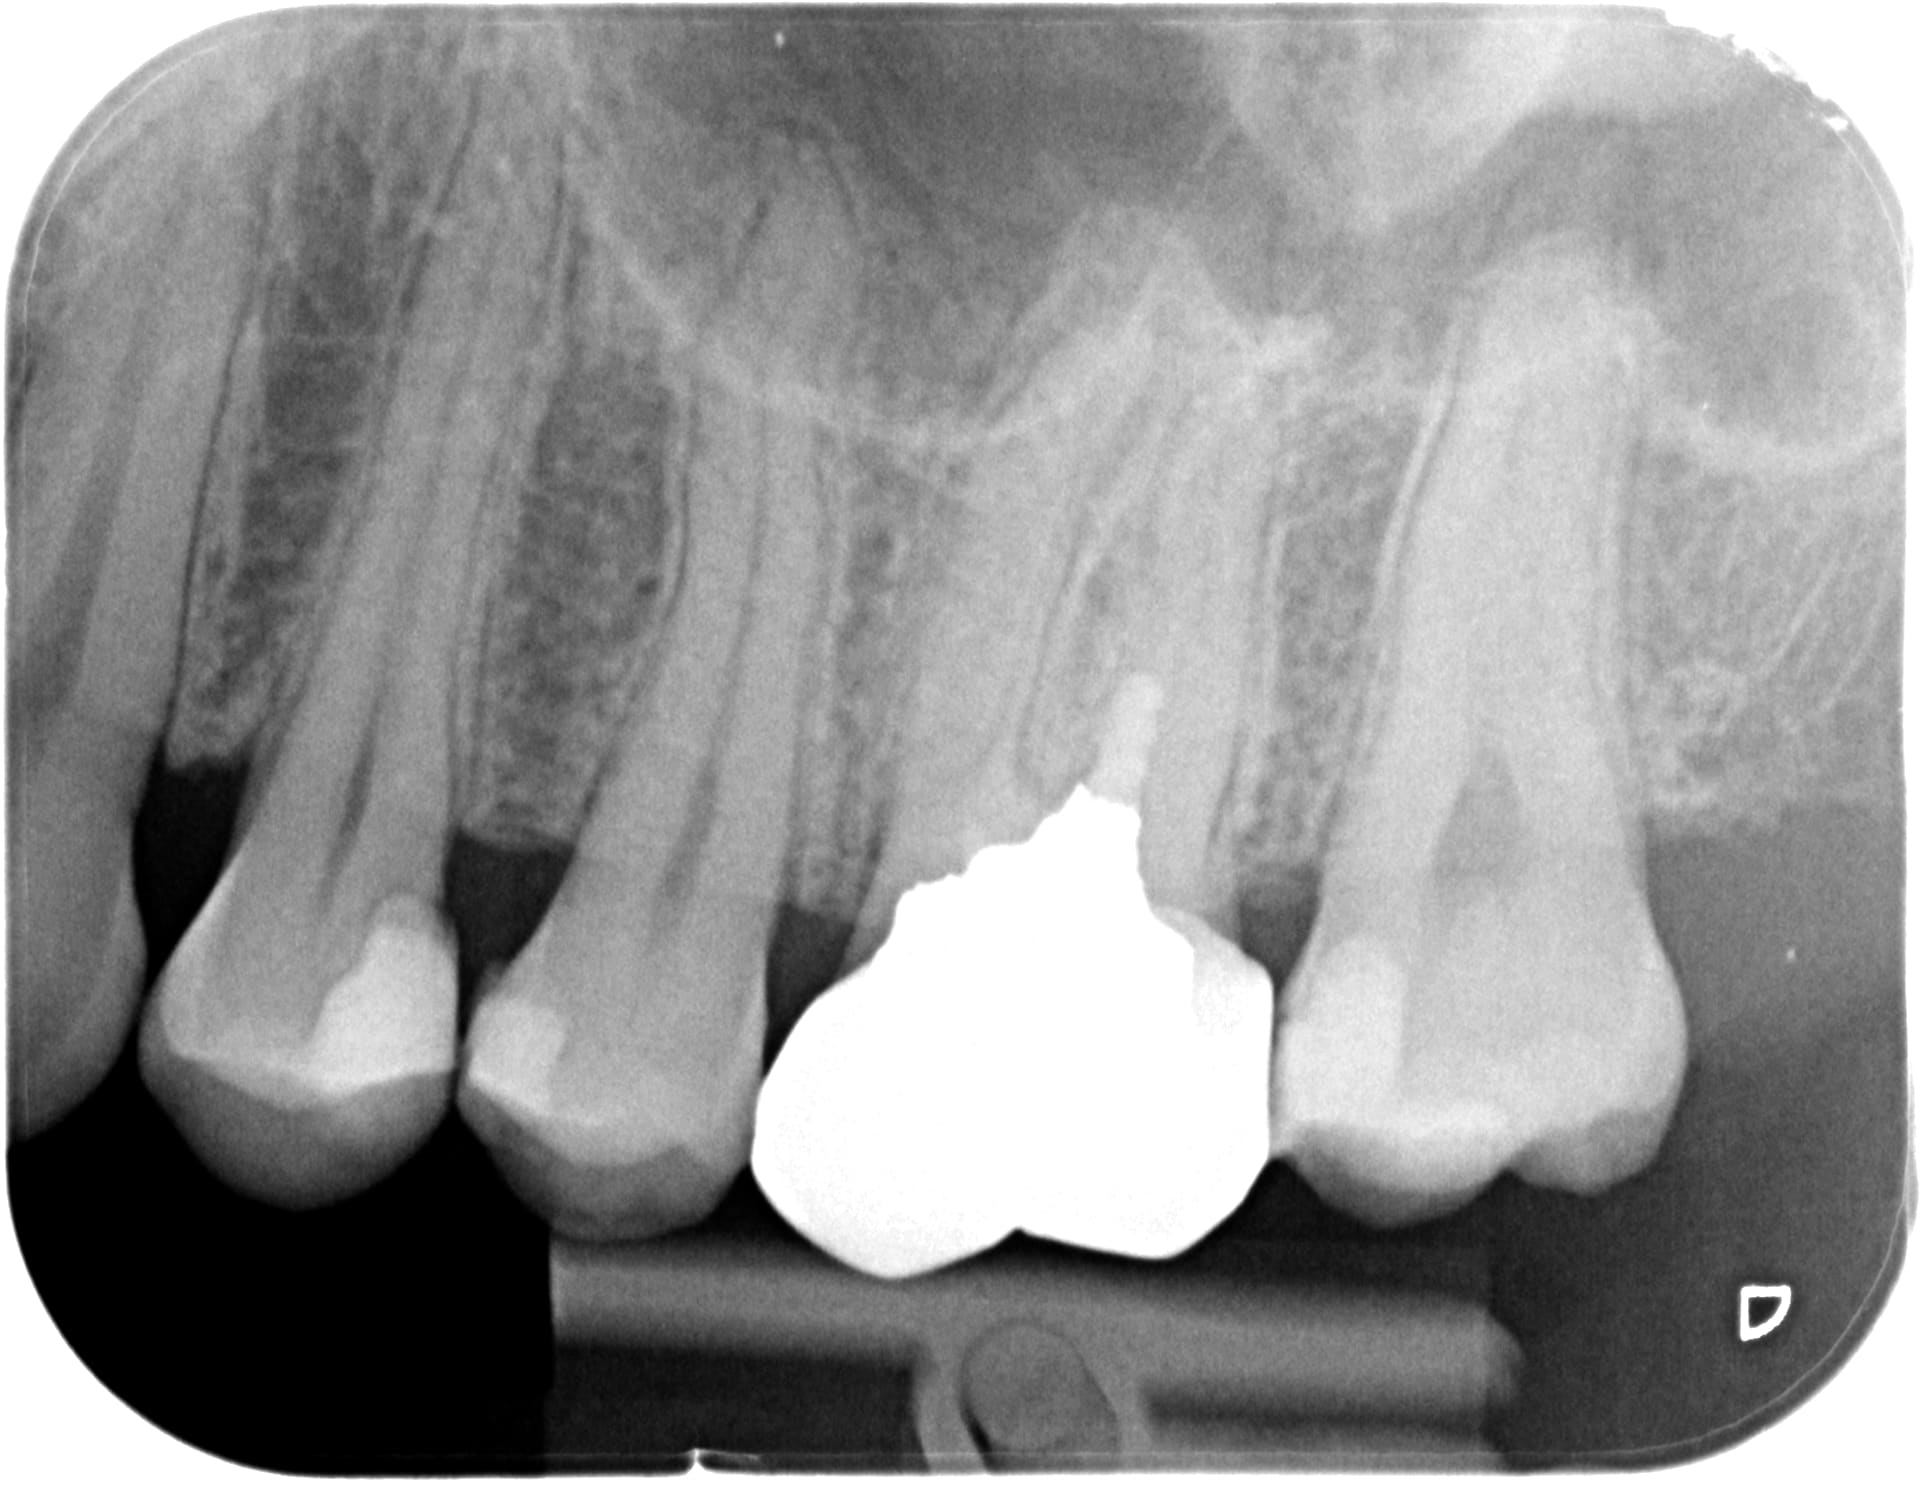

moi je fais tout bien mes controles... et c'est vrai que la priorité c'est la qualité des radios. (j'en ai des bien mieux mais je retrouve plus le dossier...)

488 x 20171031 143047 x0raxcqieext 4 hoprxn - Eugenol

1536 x 20170912 185521 xxps5fdi7wv  4 zqtipo - Eugenol

1570 x 20171104 093932 xryufeigfwma 3 bnuqdo - Eugenol

1825 x 20180814 173735 xkh4f3zz8djs 4 fuedvz - Eugenol